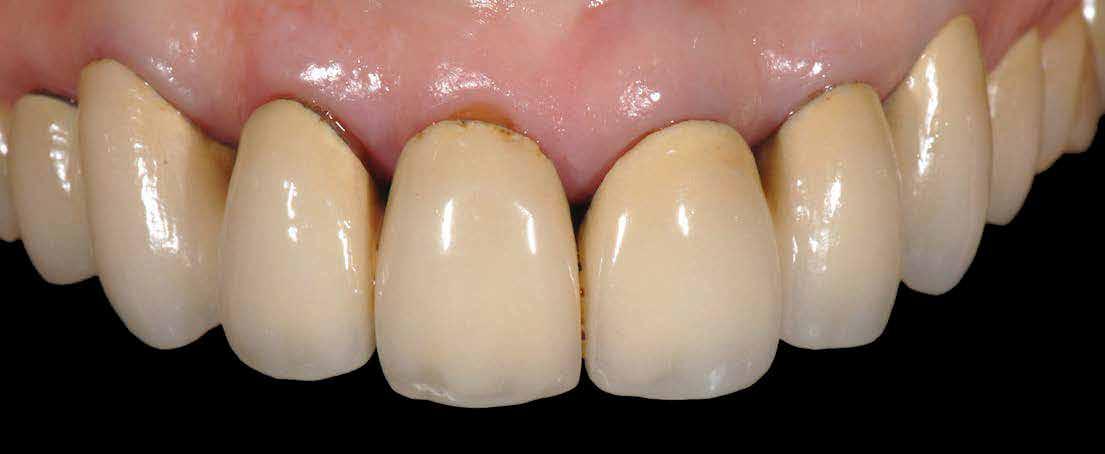

Dr. Marco Nicastro (Olaszország) A kiindulási állapot és a végeredmény. A KATANA™ UTML kiváló esztétikai tulajdonságokkal rendelkezik, és tökéletesen, harmonikusan illeszkedik a rózsaszín szövetekkel.

1. ábra: A beteg esztétikai problémájára kért megoldást a régi restaurációk természetellenes megjelenése, továbbá a múltban lezajlott periodontitis következtében kialakult fekete háromszögek miatt. A szövetek visszahúzódása következtében a fogpótlás széle jól láthatóvá vált, a papilla csúcsok elvesztése és a koronák közötti számos fekete térrel együtt, komplex terápiás ellátást igényelt.

16. ábra: Klinikai fotó egy évvel a PANAVIA V5-tel történő beragasztás után. A marginális szövetek jó klinikai állapotát látjuk, semmi jele gyulladásnak vagy vérzésnek. A BOPT lehetővé teszi számunkra, hogy optimalizáljuk a gingiva szintjét anélkül, hogy parodontológiai sebészeti beavatkozáshoz folyamodnánk, miközben az új koronák alakja lehetővé tette az interproximális terek zárását az optimális esztétikai eredmény érdekében.

17. ábra: A fogpótlás világossága (főleg a transzlucentes cirkónium használatának köszönhetően), a metszők alakjával kombinálva nagymértékben javította a pótlás esztétikáját, még akkor is, ha a kiindulási helyzet különösen kedvezőtlennek tűnt.

18. ábra: Az előző fogpótlással összehasonlítva a metszők redukálása nem csak azt tette számunkra lehetővé, hogy optimalizáljuk a funkcionális fázist az overjet csökkentésével, hanem lehetővé tette a még esztétikusabb eredmény elérését azzal, hogy a metszők élének kontúrjával követni tudtuk az alsó ajkat.